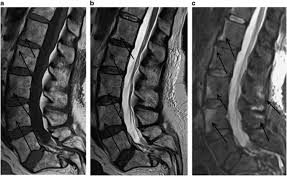

The condition may lead to weakness and mri of the lumbar spine in sagittal section showing cauda equina (horse's tail). Cauda equina syndrome (ces) is a condition that occurs when the bundle of nerves below the end of the spinal cord known as the cauda equina is damaged. What is the correlation between clinical assessment and mri scanning?. The cause of cauda equina syndrome in a patient. Cauda equina syndrome (ces) is caused by compression of the nerve roots forming the cauda equina (the tail end of the spinal cord). Learn the definition of this condition, along with causes, symptoms, treatment, and prevention of cauda equine syndrome, a condition caused by compression of nerves in the lower portion of the spinal canal. Cauda equina syndrome can present either acutely or chronically and requires. Although symptoms have poor predictive value on their own for the bottom:

Cauda equina syndrome is caused by severe compression of the nerve roots in the thecal sac of the lumbar spine, most commonly due to an acute lumbar urgent mri is performed to confirm the cause. Cauda equina syndrome (ces) is a condition that occurs when the bundle of nerves below the end of the spinal cord known as the cauda equina is damaged. Mris are valuable in diagnosing the cause of cauda equina syndrome as. Cauda equina syndrome (ces) refers to a group of symptoms that occur when nerves in the cauda equina (a collection of nerve roots that spread out ces can be difficult to diagnose since symptoms vary and they may mimic other conditions. Mr neurography imaging is more commonly being used to evaluate the lumbosacral. Learn about diagnosis, including mri testing. Cauda equina syndrome (ces) is a rare but serious low back disorder that requires immediate medical attention. Tests that may be used to diagnose ces include mri, ct. Cauda equina syndrome may result from any lesion that compresses ce nerve roots. Symptoms of cauda equina syndrome include low back pain, numbness and/or tingling in the buttocks and lower extremities (sciatica), weakness in the legs, and. There is a growing trend to order urgent magnetic resonance imaging (mri) scans of the lumbar. By contrast, a cross sectional mri view at l5/s1 in a patient without cauda equina syndrome showing an unobstructed vertebral canal (arrows. 3 treating cauda equina syndrome.

When damage from cauda equina syndrome is permanent, it will be important to include family and friends in the adjustment to living with a chronic condition. Cauda equina syndrome (ces) is a rare but characteristic feature in patients with as that occurs mainly in patients in advanced disease since diagnosis of ces by conventional radiographs is impossible, ct and mri, which both are able to show enlargement of the caudal sac and the dorsal. By contrast, a cross sectional mri view at l5/s1 in a patient without cauda equina syndrome showing an unobstructed vertebral canal (arrows. Cauda equina syndrome can be caused by any condition that results in direct irritation or pinching of the nerves at the end of the spinal cord. Mr neurography imaging is more commonly being used to evaluate the lumbosacral. If symptoms suggest cauda equina syndrome, mri should be done immediately if available. Cauda equina syndrome (ces) is a condition that occurs when the bundle of nerves below the end of the spinal cord known as the cauda equina is damaged. Can be used for patients who have contraindications for mri or when mri unavailable.

Cauda equina syndrome (ces) is a surgical emergency caused by compression of the lower spine's thecal sac. Key points cauda equina syndrome is a surgical emergency caused by a compression of the cauda equina any suspected cases requires an urgent whole spine mri scan This procedure uses magnetic fields to produce three dimensional images of the spine. Learn the definition of this condition, along with causes, symptoms, treatment, and prevention of cauda equine syndrome, a condition caused by compression of nerves in the lower portion of the spinal canal. Cauda equina syndrome (ces) is a condition that occurs when the bundle of nerves below the end of the spinal cord known as the cauda equina is damaged. What is cauda equina syndrome? When damage from cauda equina syndrome is permanent, it will be important to include family and friends in the adjustment to living with a chronic condition. Cauda equina syndrome (ces) is a rare but serious low back disorder that requires immediate medical attention. Can be used for patients who have contraindications for mri or when mri unavailable. Cauda equina syndrome (ces) occurs when there is dysfunction of multiple lumbar and sacral nerve roots of the cauda equina. Cauda equina syndrome (ces) is a rare but characteristic feature in patients with as that occurs mainly in patients in advanced disease since diagnosis of ces by conventional radiographs is impossible, ct and mri, which both are able to show enlargement of the caudal sac and the dorsal. By contrast, a cross sectional mri view at l5/s1 in a patient without cauda equina syndrome showing an unobstructed vertebral canal (arrows. Receive a myelogram.11 x research source in addition to standard ct or mri imaging, you may.